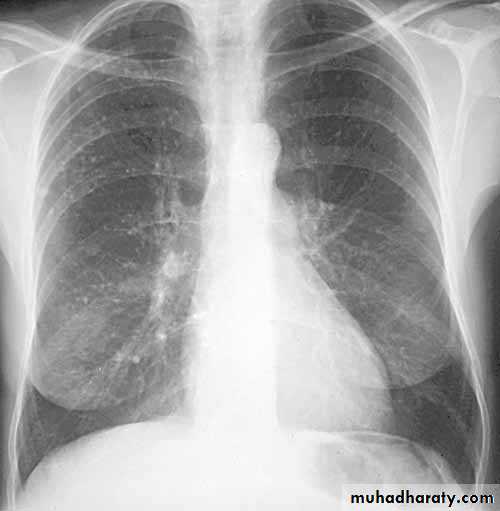

Cannon ball secondaries